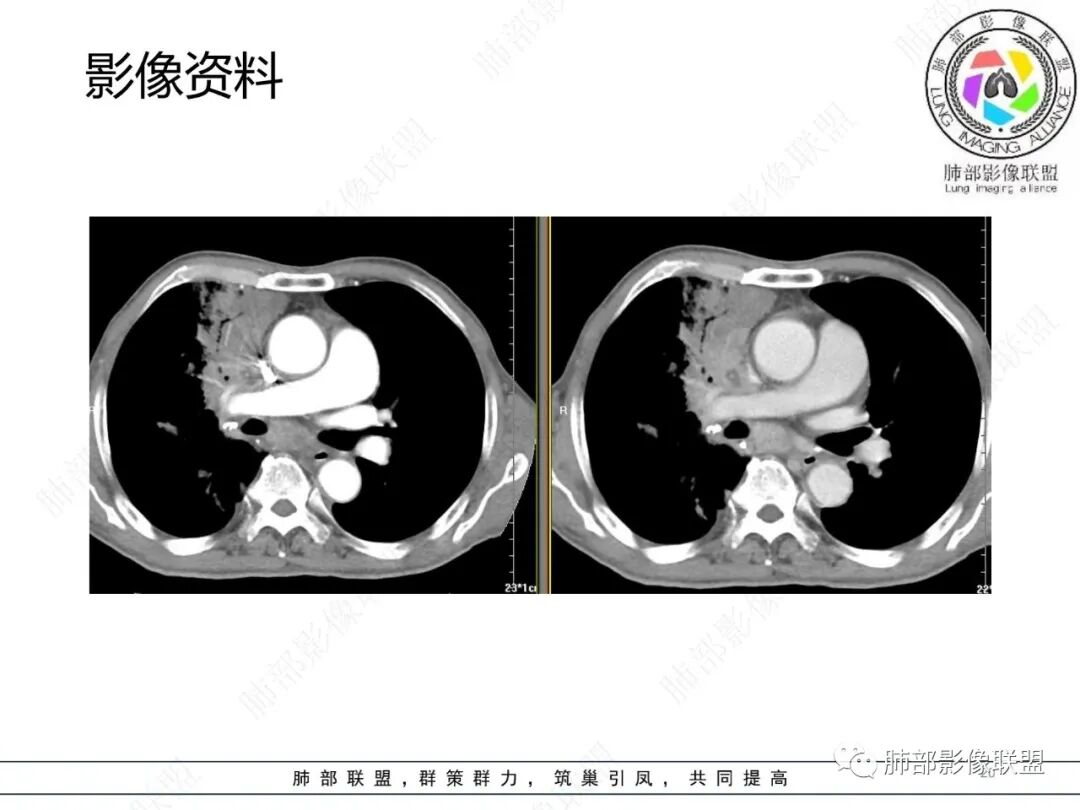

影像资料

2.胸部CT: 右肺病灶,主要累及右肺上叶前段、右肺中叶内侧段及右肺下叶背段,片状影及结节影,实性密度为主,部分磨玻璃晕,密度不均,散在钙化,其中上叶前段支气管闭塞,隐约见钙化突入。未见明确“硬树芽”或“拐枣征”。主要呈延迟强化,其间低密度区疑坏死或粘液成分。纵隔内见多组淋巴结肿大环形强化,部分钙化。

临床免疫缺陷患者呼吸系统症状易想到肺孢子菌或马尔尼菲篮状菌感染。影像不支持肺孢子菌肺炎。马尔尼菲篮状菌肺部感染影像表现多样,可以磨玻璃影、实变影,有时多发结节影酷似继发性肺结核,纵隔或远处淋巴结肿大并环形强化等须仔细甄别。有文献报道马尔尼菲篮状菌肺部感染患者82.7%胸部CT有异常改变,胸部CT表现:45.6%患者肺野斑片状浸润阴影或局限性肺实变,11.9%患者表现为结节影,11.5%患者表现为毛玻璃改变,8.4%患者表现为弥漫性粟粒样病变,5.3%患者表现为结节状肿块影。45.1%患者胸部影像学伴肺门或纵隔淋巴结肿大,23.5%患者伴胸腔积液,8.0%伴空洞病灶。